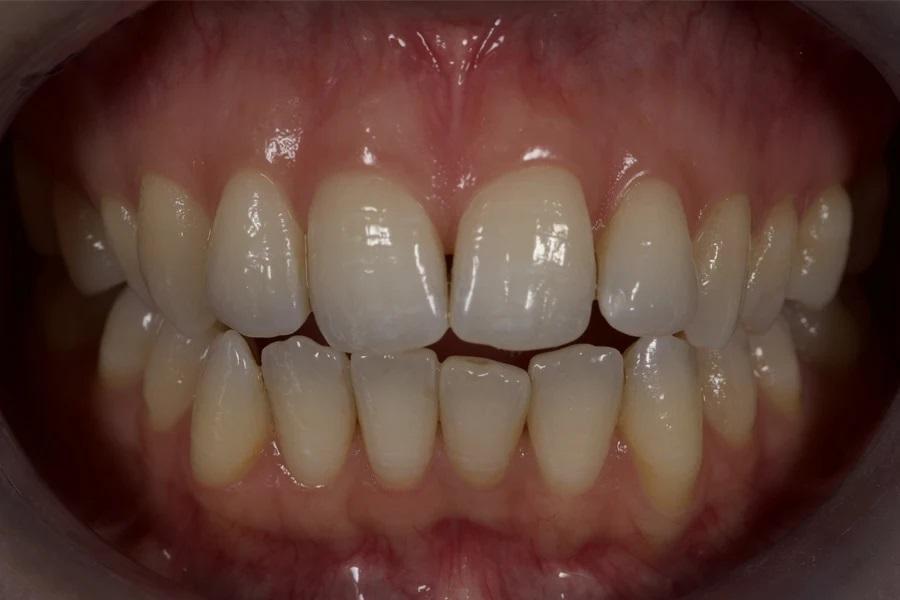

Фото 12. Окончательный результат после ортодонтического лечения. Отмечаются закрытие открытого прикуса, коррекция торка/выравнивание осей зубов и формирование окклюзионных контактов по сравнению с исходным состоянием.

Фото 1. Исходная внутриротовая оценка в положении максимальной интеркуспидации. Отмечаются передний открытый прикус, скученность зубов с отрицательным торком коронок, начальные стадии «черных треугольников» (особенно между зубами 11 и 21), асимметричные «провисающие» задние щечные коридоры верхней челюсти и тонкий биотип, предрасполагающий к рецессиям, особенно у молодых пациентов.